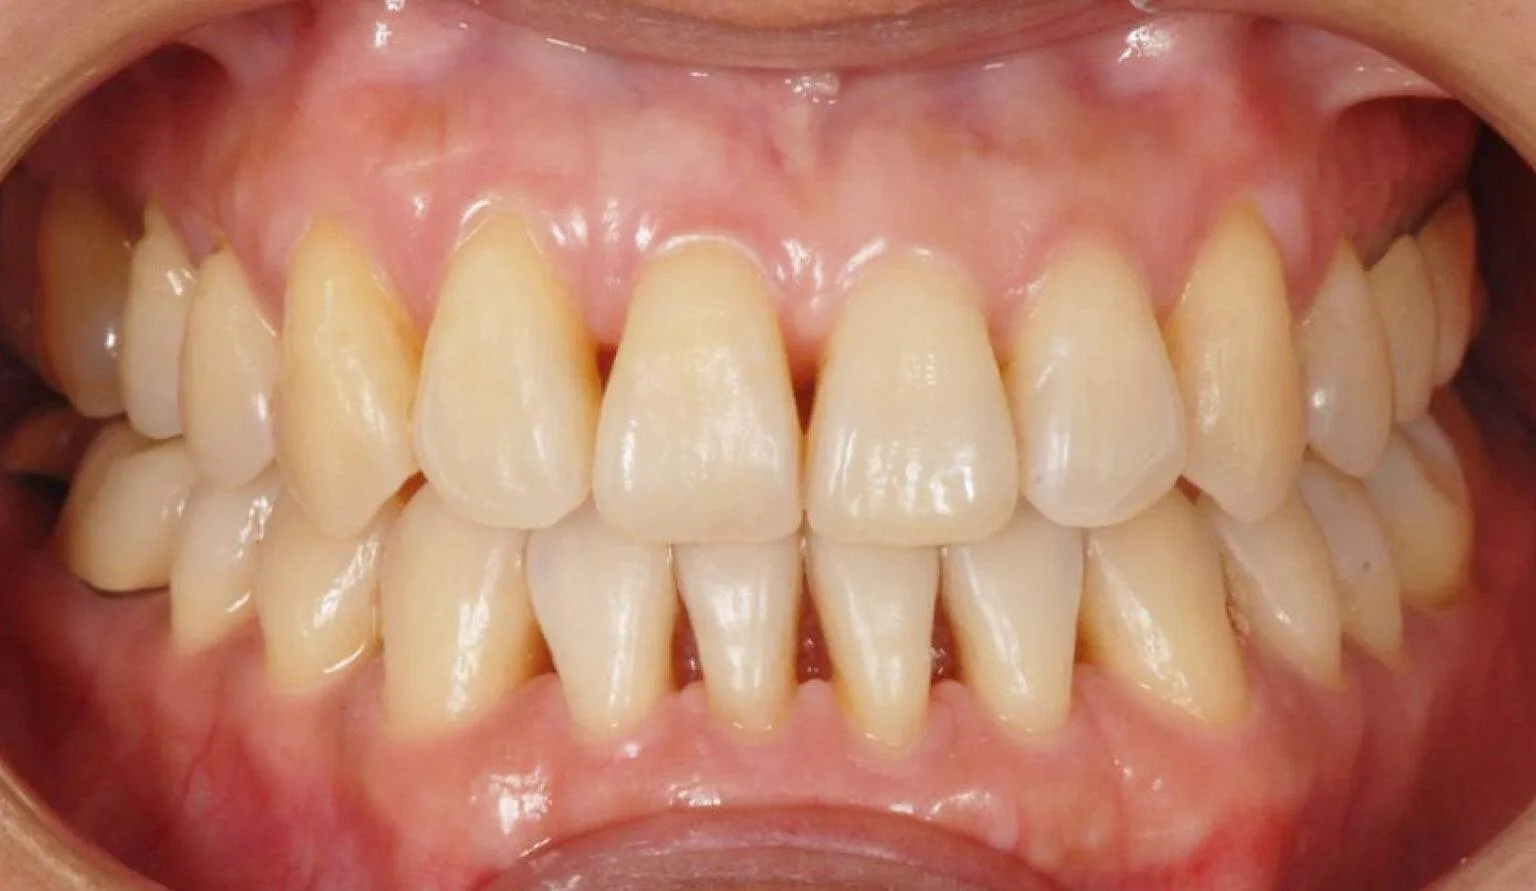

Before overcrowding treatment at SmileBox Clinic After overcrowding treatment at SmileBox Dental Clinic